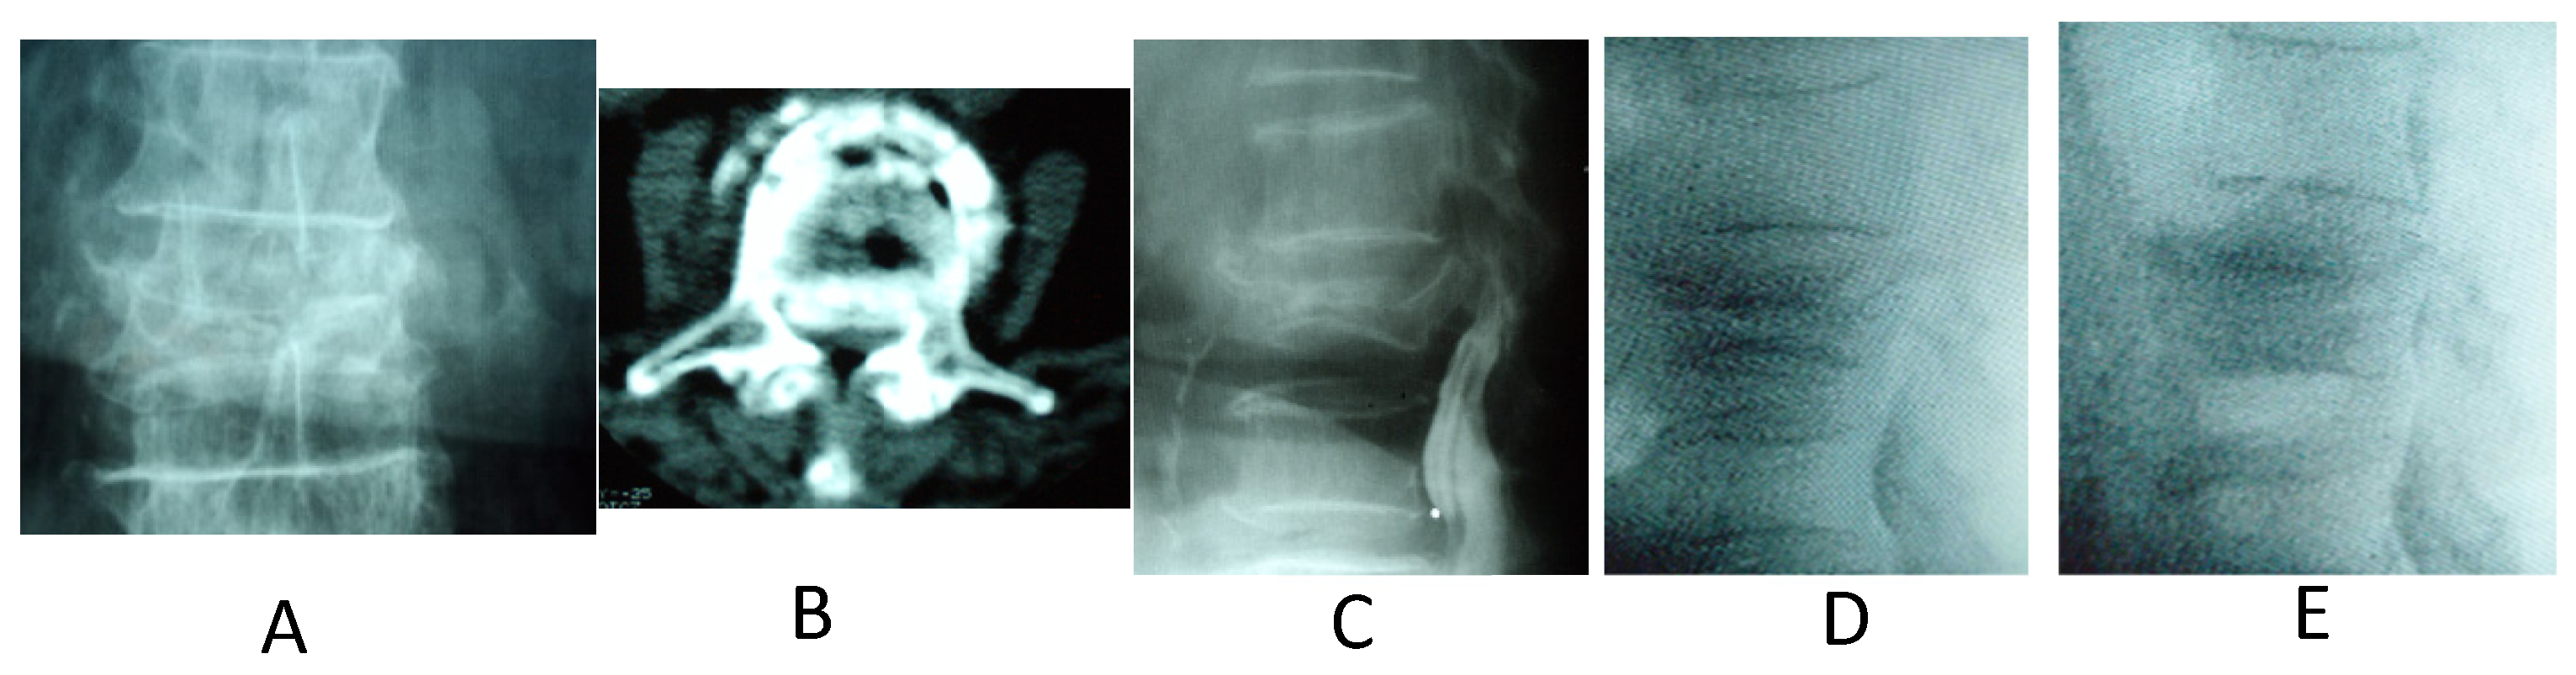

2. Materials and Methods

3. Results

4. Discussion